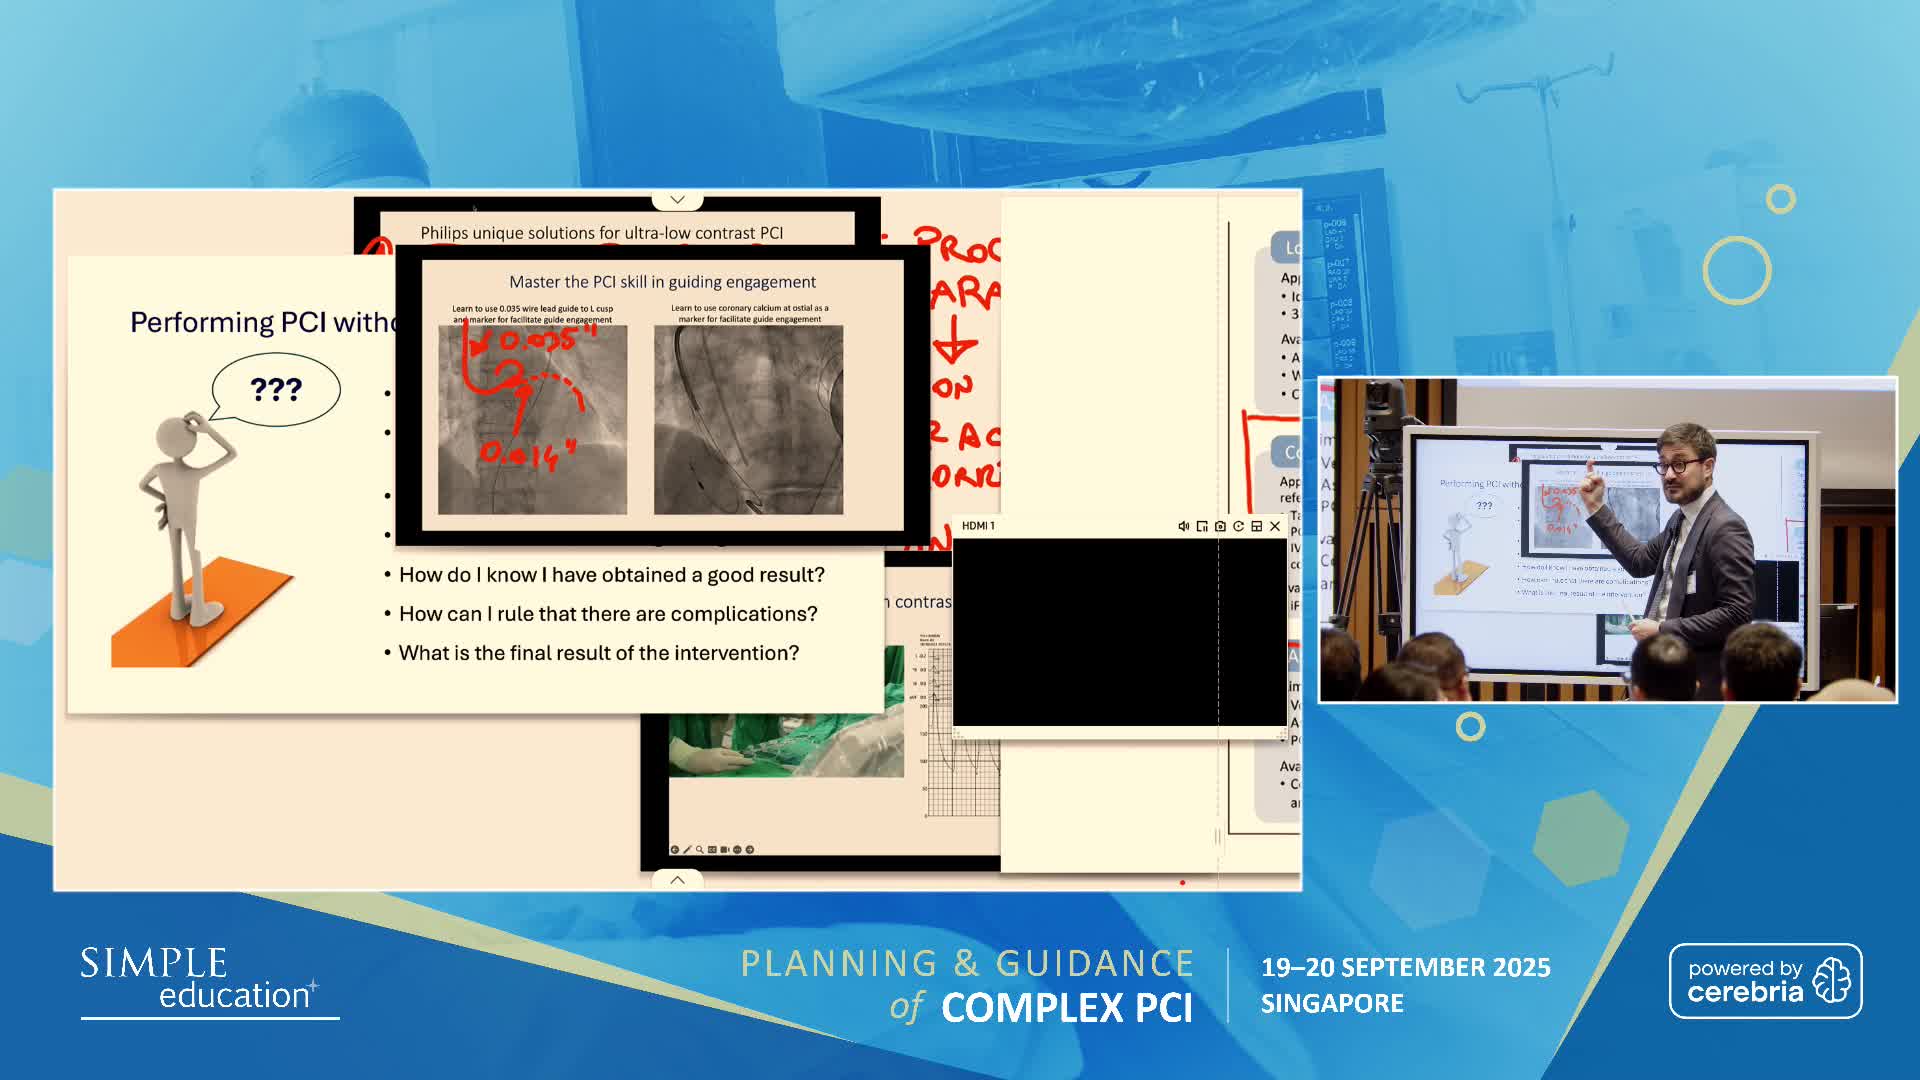

Ultralow Contrast PCI in complex and high risk patients - April 2024 Day One

Ultralow Contrast PCI in complex and high risk patients - April 2024 Day Two

Ultralow Contrast PCI in complex and high risk patients - November 2023 Day One

Ultralow Contrast PCI in complex and high risk patients - November 2023 Day Two

Ultralow Contrast PCI in complex and high risk patients - June 2023 Day One

Ultralow Contrast PCI in complex and high risk patients - June 2023 Day Two